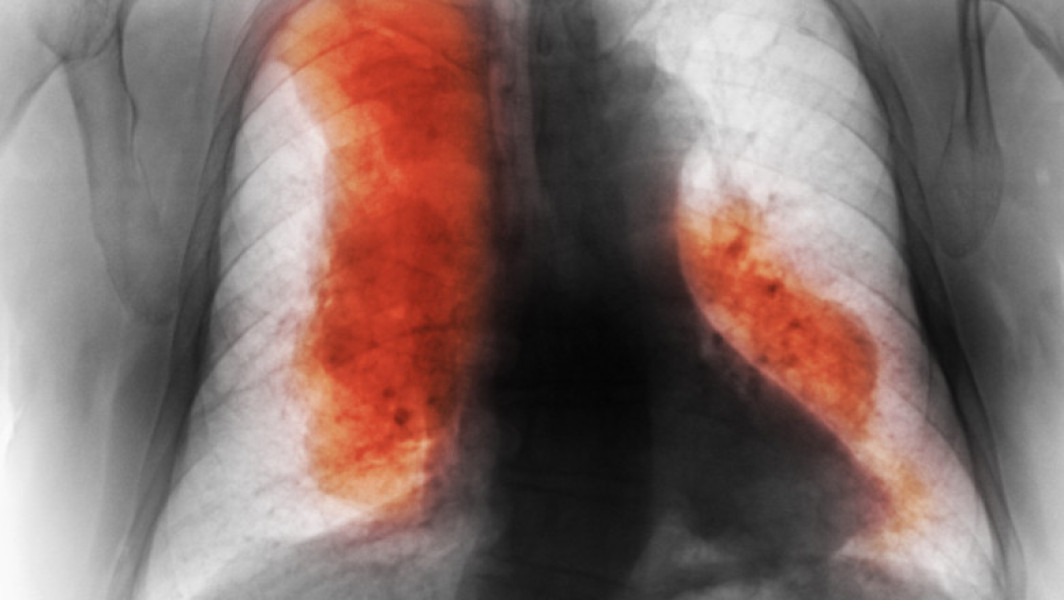

Cercetarea publicată în jurnalul The Lancet acoperă 204 ţări şi include date despre 47 de tipuri de cancer. În 2023, s-au înregistrat aproximativ 18,5 milioane de cazuri noi şi 10,4 milioane de decese, o creştere de 74% faţă de 1990. Cancerul mamar a fost cel mai des diagnosticat, însă cel mai letal rămâne cel pulmonar.